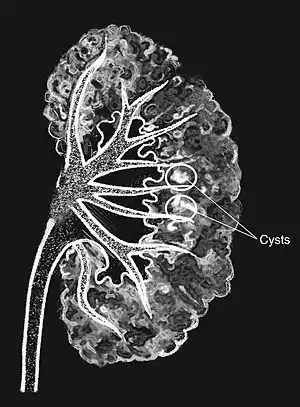

The cause is unclear.[2] Most cases do not appear to be inherited from a persons parents.[2] The underlying mechanism involves dilation of the collecting ducts and tubules in the renal pyramids.[3] One or both kidneys may be involved.[2] Diagnosis may be supported by medical imaging.[2]

Classically, MSK is seen as hyperechoic papillae with clusters of small stones on ultrasound examination of the kidney or with an abdominal x-ray. The irregular (ectatic) collecting ducts are often seen in MSK, which are sometimes described as having a "paintbrush-like" appearance, are best seen on intravenous urography. However, IV urography has been largely replaced by contrast-enhanced, high-resolution helical CT with digital reconstruction.[9]